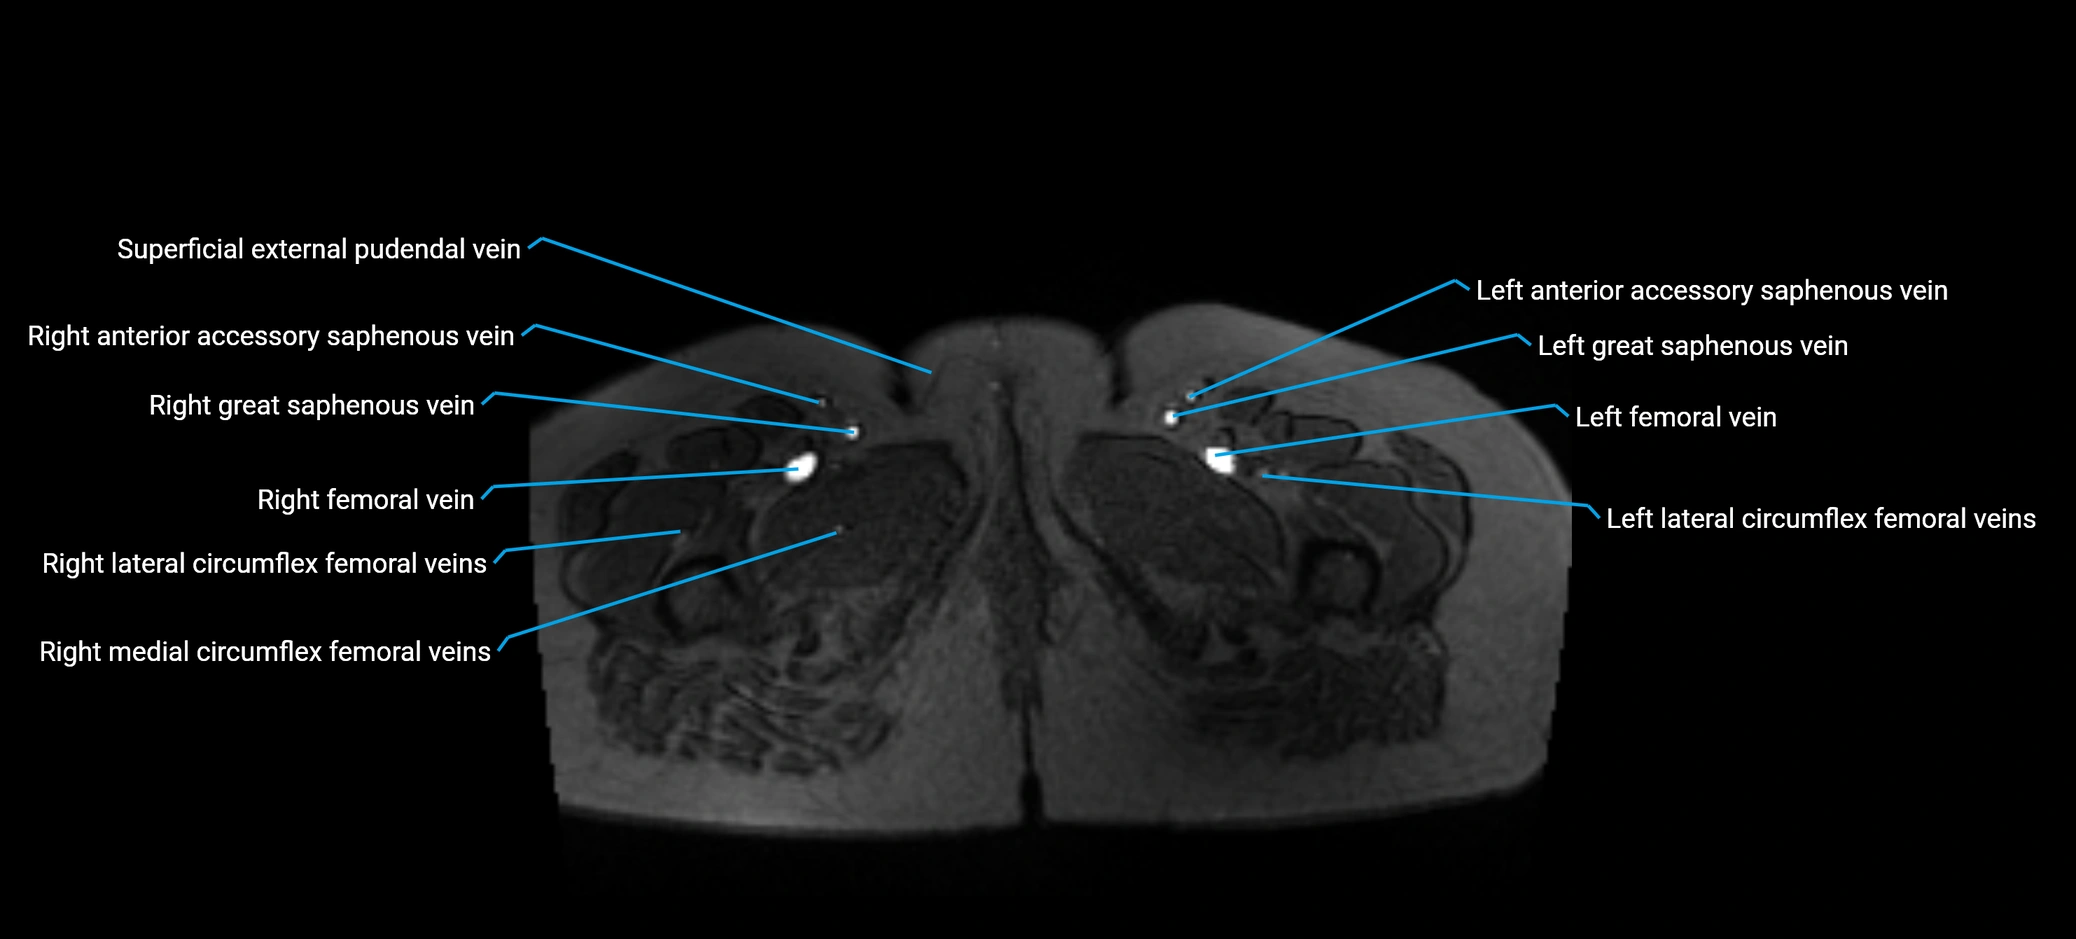

MRI image

image